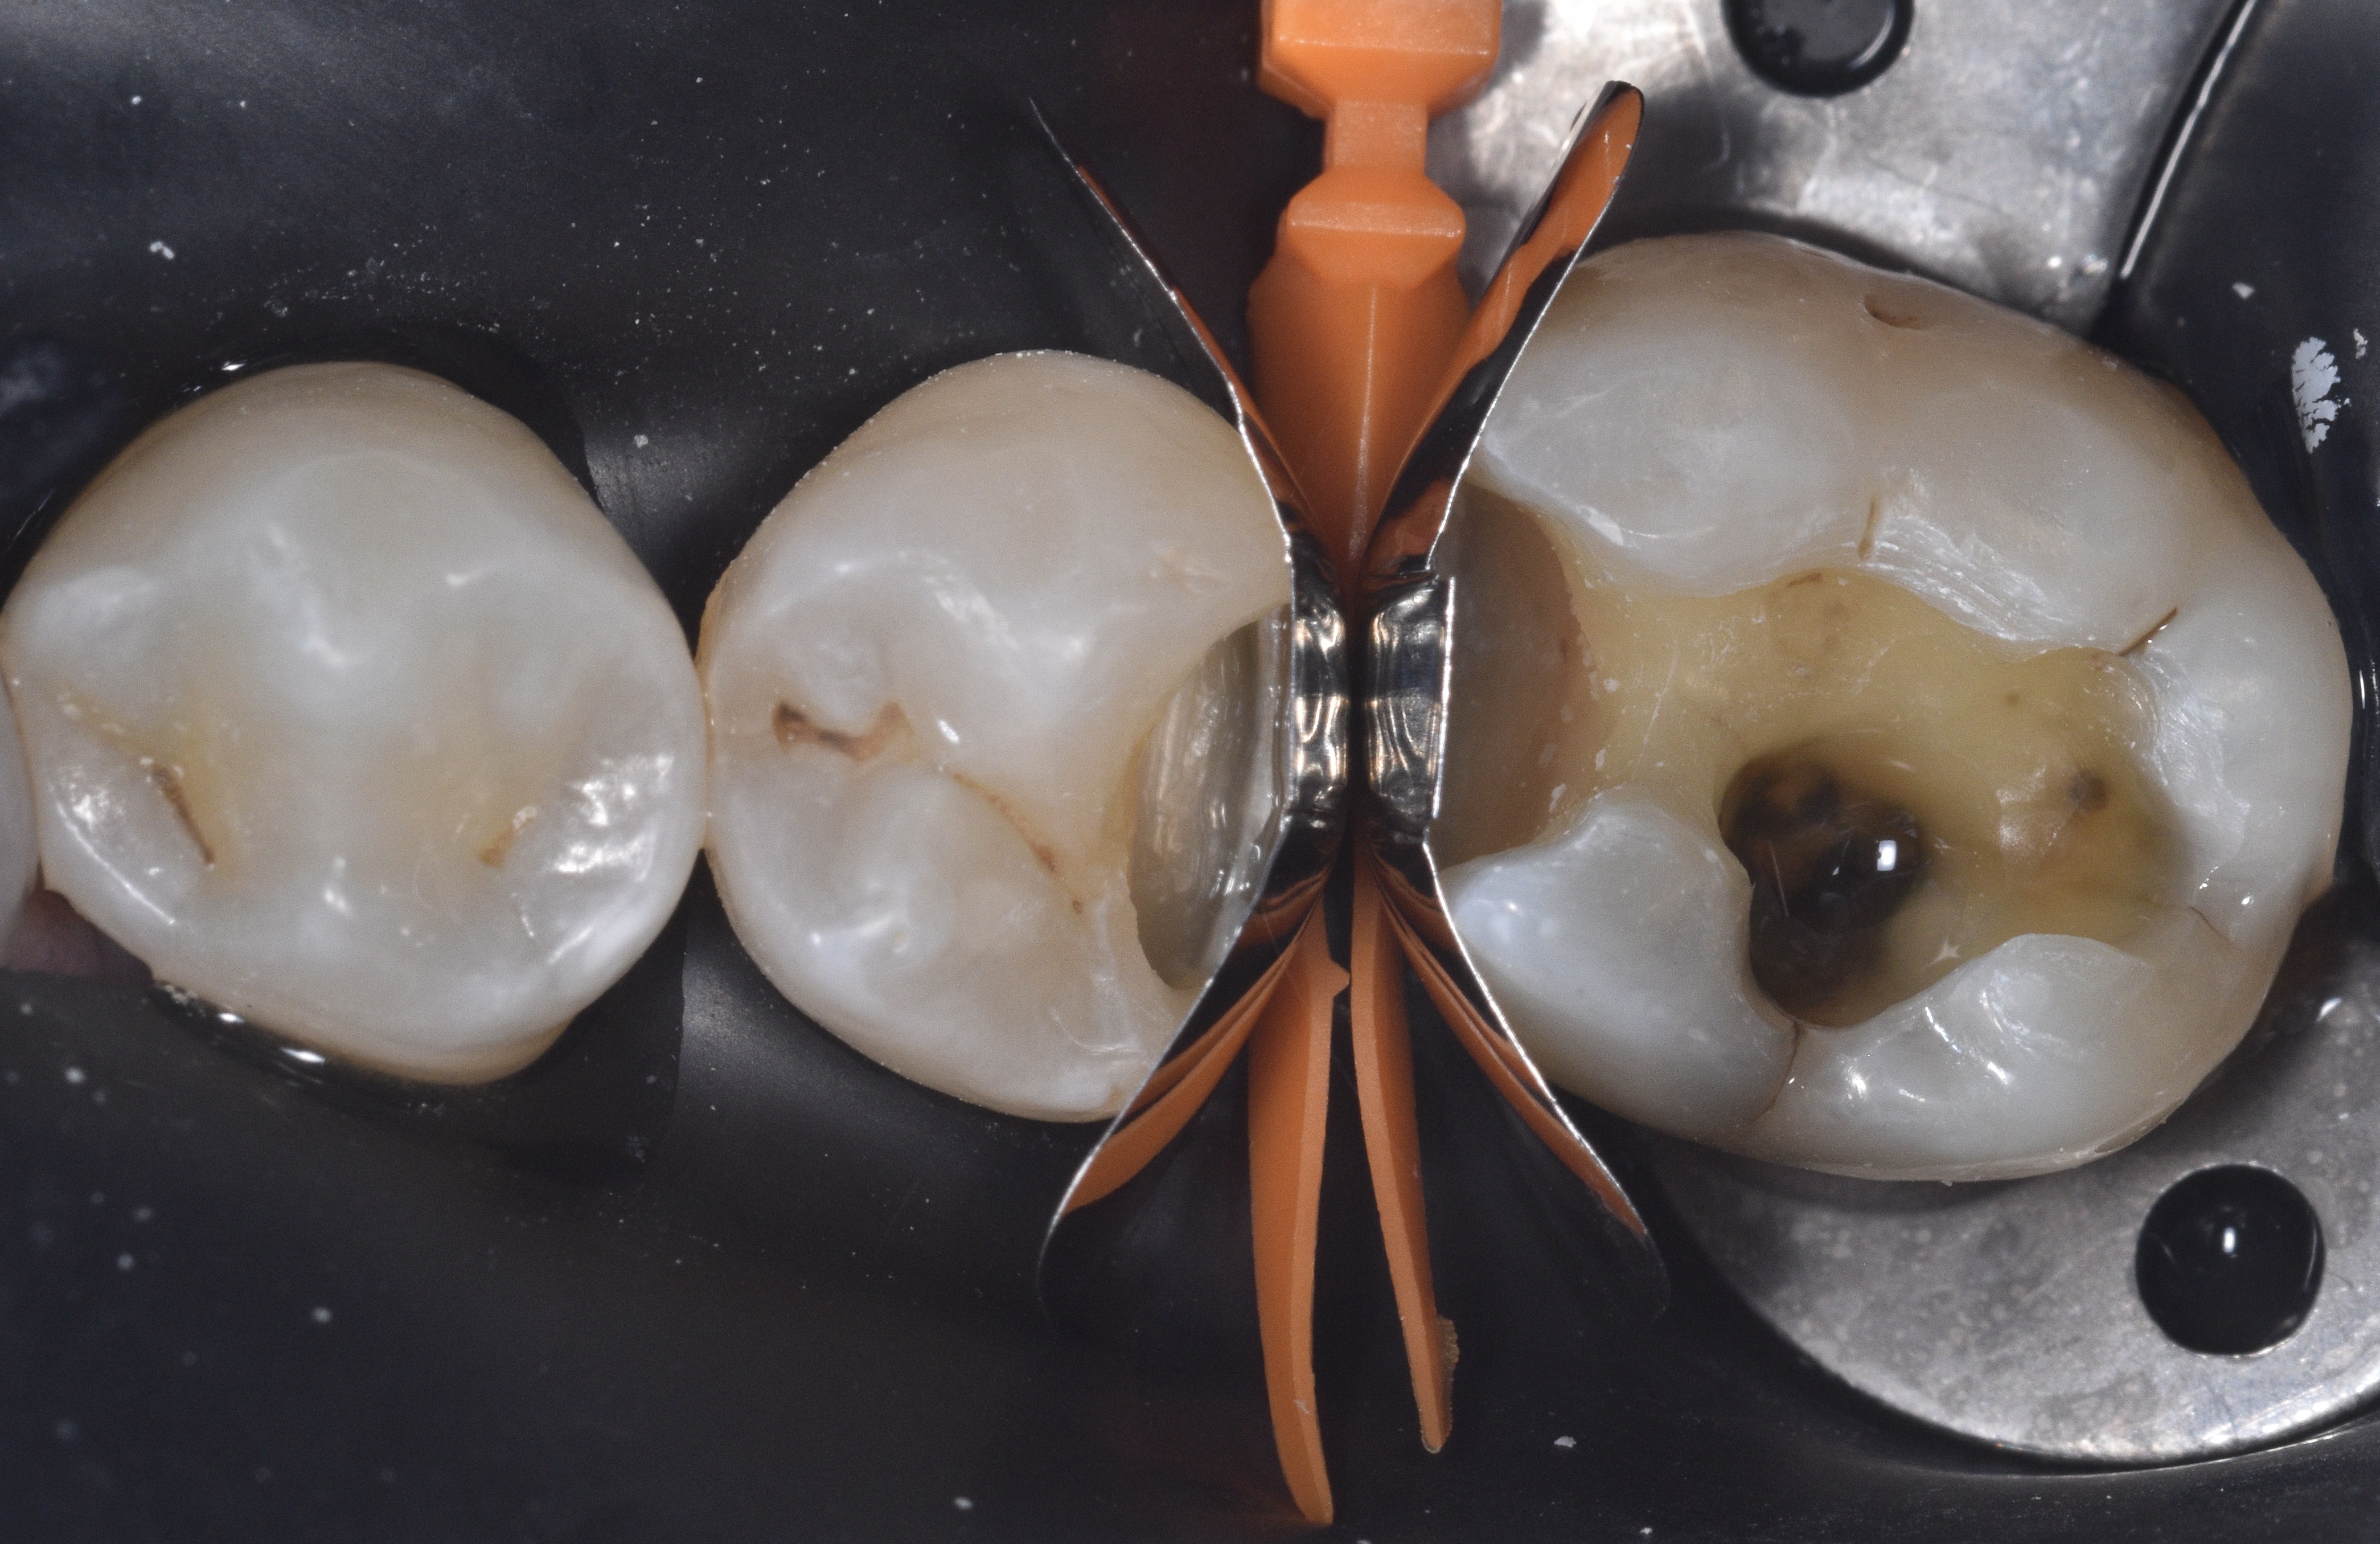

Figures 4 and 5 display the selected QUAD wedge and ring system for this case. The ring features an arrow-shaped driver tip (Figure 6) that fits into the split portion of the wedge, pressing the matrix bands mesially and distally to improve adaptation to the tooth contours. In Figure 7, the medium QUAD wedge securely holds the firm stainless-steel matrix bands in place, while Figure 8 illustrates the placement of the ring and the action of the driver tip in splitting the wedge on the lingual surface, enhancing the contouring of the bands.

Figure 6. The Quad ring driver tip designed to fit into the split portion of the wedge.Figure 7. Medium Quad wedge securely holding the firm stainless-steel matrix bands in place.Figure 8. Quad system placement shown enhancing the contour of the bands.

However, it is important to note that the band could not be fully adapted to the distal-lingual margin of the proximal box on tooth #29. This limitation made simultaneous restoration of both teeth unsuitable for this clinical scenario. Consequently, the decision was made to restore one tooth at a time while keeping both sectional matrices in place to prevent interference between restorations.